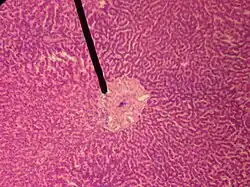

![]() A single lobule of the liver of a pig. X 60. (Central vein not labeled, though region is visible. Central vein would be a single vein at the center of the lobule.) | |

In microanatomy, the central veins of liver (or central venules)[1] are veins found at the center of hepatic lobules (one vein at each lobule center).

They receive the blood mixed in the liver sinusoids and return it to circulation via the hepatic veins.[2]